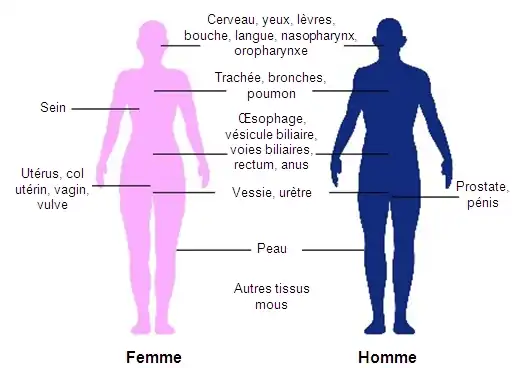

La curiethérapie est couramment utilisée pour traiter les cancers du col de l'utérus[21] de la prostate[19], du sein[20], et de la peau[22]. Elle peut également être utilisé dans le traitement des tumeurs du cerveau[32], de l'œil[33], de la tête et du cou (lèvre, le plancher de la bouche, la langue, du nasopharynx et de l'oropharynx)[24], des voies respiratoires (la trachée et les bronches)[28], des voies digestives (œsophage, de la vésicule biliaire, voies biliaires, du rectum, anus)[27],[34],[35],[36], des voies urinaires (vessie, l'urètre, du pénis)[37],[38],[39], de l'appareil reproducteur féminin (utérus, du vagin, vulve)[40],[41], et des tissus mous[25].